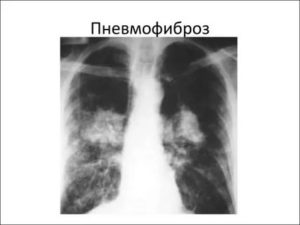

В медицинской практике встречается пневмофиброз локального и диффузного вида. Заболевание локального типа характеризуется уплотнением отдельного фрагмента легкого. Явных нарушений газообменных процессов не наблюдается. Диффузный пневмофиброз легких приводит к тому, что они утрачивают первоначальную структуру и форму, увеличивается их плотность, нарушается вентиляция.

При пневмофиброзе образуется повышенное количество соединительной ткани за счет коллагена, в связи с чем утрачивается эластичность легочной ткани, значительно снижается функция газообмена, поскольку коллаген откладывается и в стенках альвеол, и прогрессирует дыхательная недостаточность. От распространенности фиброза (локальный или диффузный) зависит степень нарушения дыхания и газообмена, течение болезни и ее прогноз.

Локальная форма — при этой форме ткань легких теряет свои функции и замещается на соединительную ткань единственный участок органа. Диффузный пневмофиброз — это одна из тяжелых форм болезни, при которой поражается ткань целого органа, а иногда и обоих легких.

Объем пораженной поверхности сильно уменьшается за счет уплотнения и деформации тканей, вентиляция нарушается.